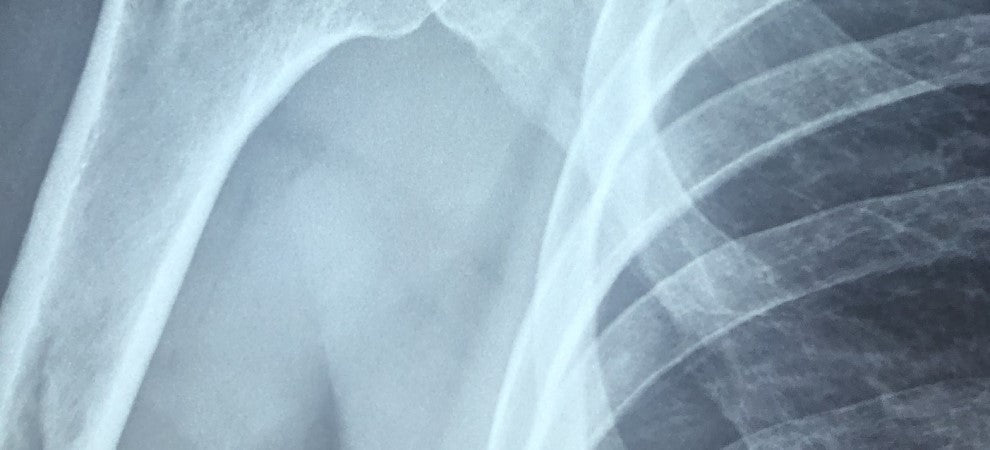

Osteoporosis is a condition that weakens your bones, making them more fragile and more likely to break. It develops slowly over time. Often, people have osteoporosis for months or even years before they get a diagnosis, or even notice any symptoms. Generally, you'll be diagnosed after a minor fall or sudden impact has caused a bone fracture. The most common bone injuries are wrist or hip fractures. Until a fracture occurs, osteoporosis is often a painless condition.Causes of Osteoporosis

In most cases, the first symptom will be a bone fracture, especially from a minor knock or bump. Wrist and hip fractures are particularly common. You might also notice back pain and muscles spasms, alongside a noticeable change to your posture or height. These are signs of spinal fractures, which can also indicate osteoporosis. Unfortunately, there are relatively few warning signs of osteoporosis. Therefore, it's important to know whether you belong to any at-risk groups. If you have any of the risk factors we've discussed above, consider making an appointment with your GP. They can give you advice to help lower your risk and refer you for tests if necessary.Diagnosis

If there is a chance that you might have osteoporosis, your GP will conduct a few tests and scans. Firstly, they might use online software to assess your risk of breaking a bone. The algorithms in these programmes give a 10-year probability of hip fractures and a 10-year probability of a major fracture in the spine, hip, shoulder or forearm. Your doctor might also refer you for a DEXA scan, which will measure your bone density. This scan is a short, painless procedure which takes less than 20 minutes, according to the NHS. They will then calculate the difference between your bone density and that of a healthy young adult. This difference is called a T score. A particularly low T score (-2.5 or lower) is a strong indicator of osteoporosis.Treatment for Osteoporosis